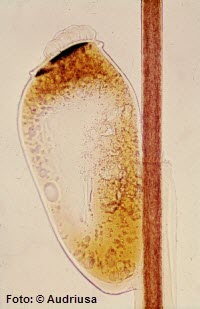

Kopflaus (Pediculus humanus

capitis)

Der Körper der Kopflaus hat eine gestreckte Form mit einer Länge von zwei bis sechs Millimetern, zu vergleichen mit einem Sesamsamen.

Der Kopf ist im Verhältnis zum übrigen Körper klein und trägt zwei reduzierte Augen.

Eier der Kopflaus

Zum Riechen und Schmecken hat die Laus die entsprechenden Sinnesorgane in einer Grube am Ende der beiden fünfgliedrigen Antennen oder Fühler.

Durch die kegelförmige, mit Zähnchen versehene Oberlippe tritt der stechend-saugende Rüssel aus, der aus Anteilen der Kiefer und dem Rachen zusammengesetzt ist.

Durch einen Kanal innerhalb dieses Saugapparates kann ein gerinnungshemmender Speichel ausgeschieden und das Blut eingesogen werden.

Der Thorax ist mit dem zehngliedrigen Abdomen verschmolzen.

Mit ihren transparenten Körpern können sich die Läuse der Haarfarbe ihres Wirtes anpassen. Nach einer Blutmahlzeit verfärben sie sich rot-bräunlich. Wie die meisten Hautparasiten sind die Läuse flügellos, denn ihre Reise führt sie nie weit.

Dafür sind ihre 6 Beine hoch entwickelt um sich in ihrem Medium, dem Kopfhaar, fortzubewegen.

Sie besitzen am Ende klammerartige Greifklauen, mit denen sie sich an den einzelnen Haaren festhalten. Mit stark ausgebildeter Muskulatur und den kugelartigen Gelenken turnt sie athletisch, wie ein Turner am Doppelbarren, in den Haaren herum.